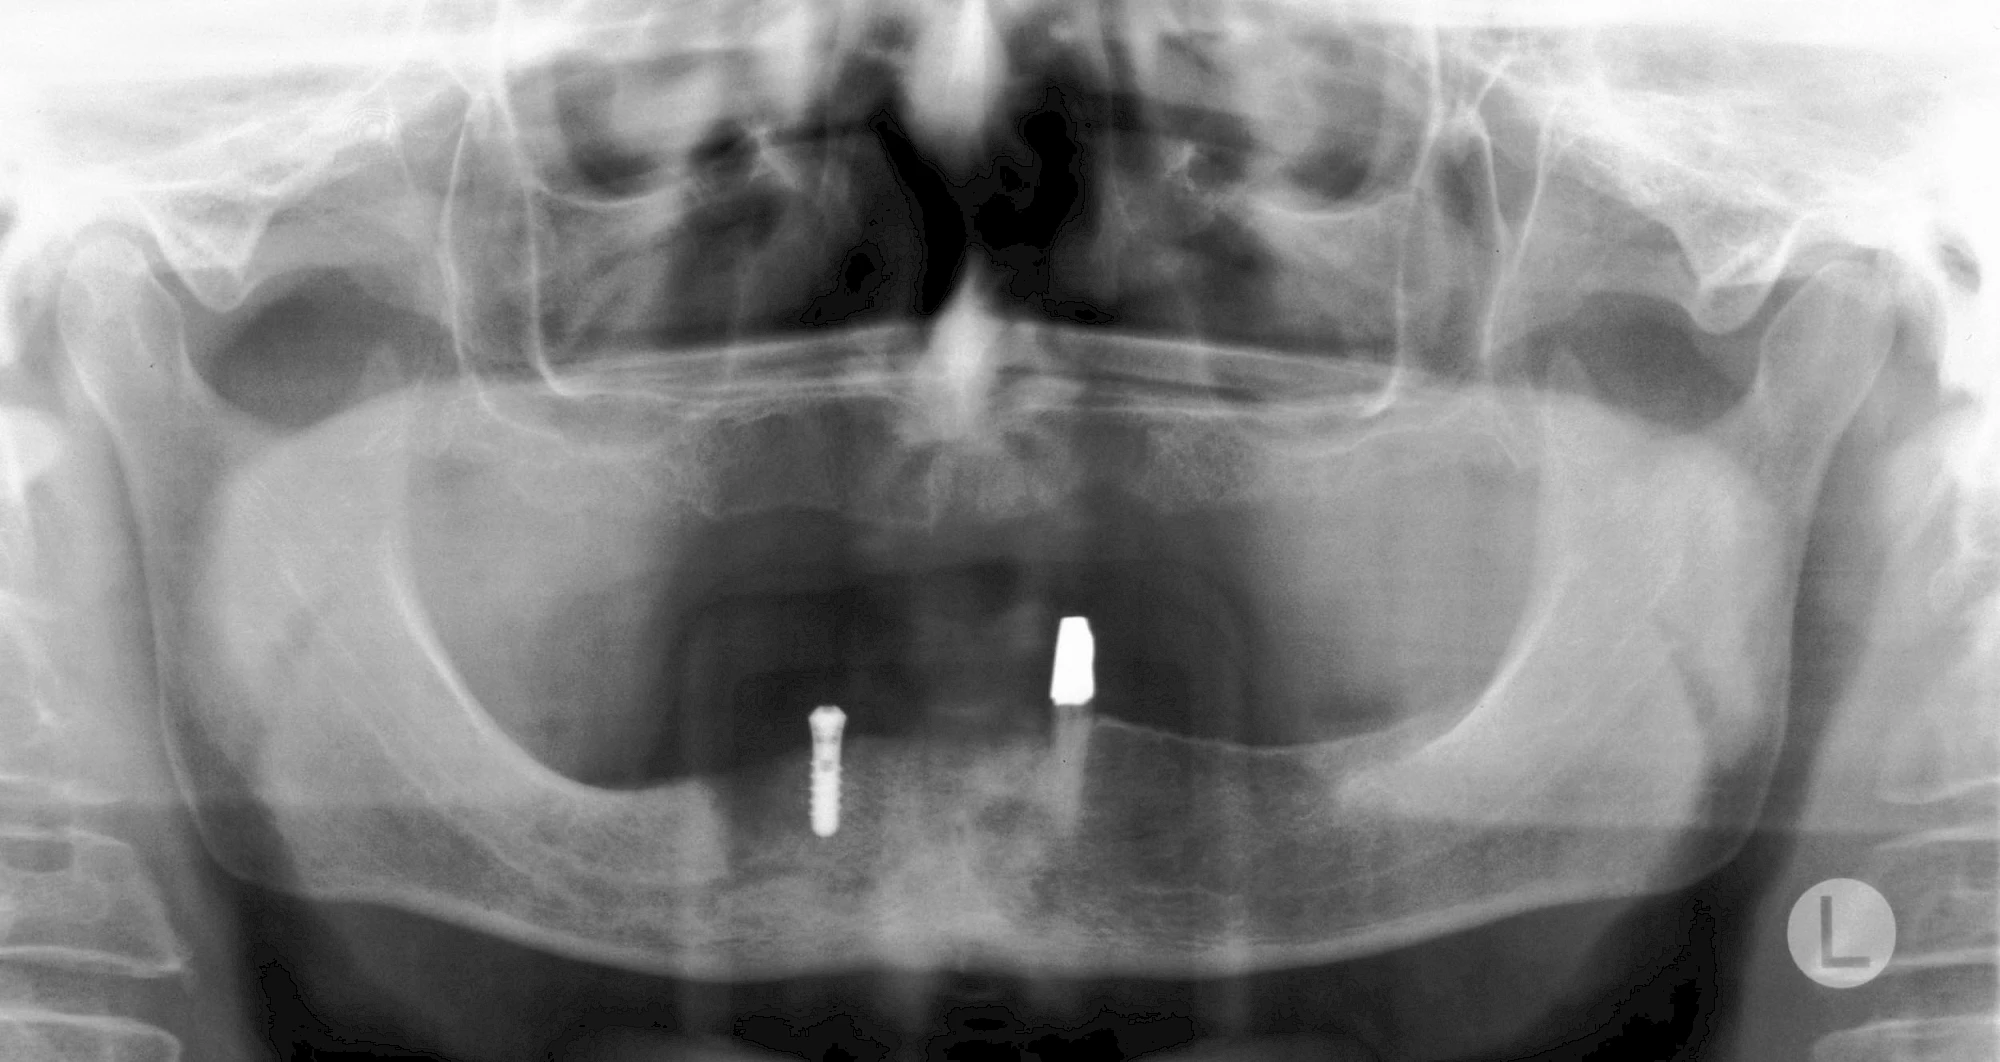

Implantatplanung

Damit Implantate an der richtigen Stelle im Kieferknochen platziert werden könen, gibt es heute vielfältige Möglichkeiten der Planung. In vielen Situationen kann die Erfahrung des Zahnarztes ausreichend sein.

Nicht selten ist jedoch auch eine technisch aufwändigere Vermessung im Vorfeld sinnvoll, z. B.:

- Wenn sich der Kieferknochen abgebaut hat

- Wenn der Nervverlauf im Unterkiefer beachtet werden muss

- Wenn die Ausdehung der Kieferhöhle im Oberkiefer beachtet werden muss

- Wenn wenige Restzähne keine gute Orientierung erlauben

In diesen Fällen kann die Planung mittels verschieden aufwendiger Röntgen-Techniken (Übersichtsaufnahme, DVT) ggf. unter Zuhilfenahme speziell angefertigter Planungsschablonen sinnvoll sein.